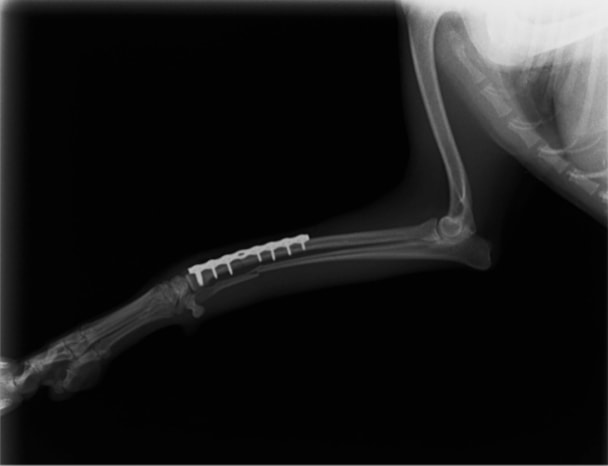

トイプードル 右遠位橈尺骨短斜骨折のALPSによる内固定